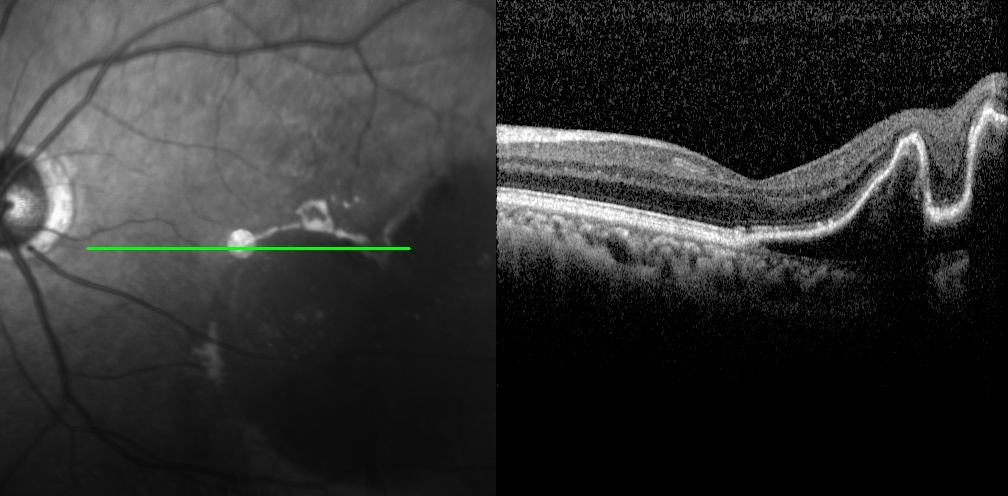

老王左眼檢查圖片

左眼調(diào)整用藥半個月后檢查圖片